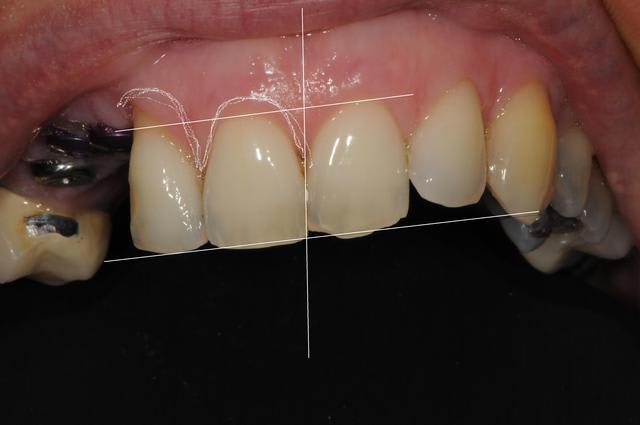

Patiente présente une perte alvéolaire de la table externe suite à fracture radiculaire.

J'ai réalisé un lambeau tracté coronairement mais je pense que certains auraient peut-être réalisé un lambeau conjonctif palatin.

Quels auraient été vos tracés d'incisions ?